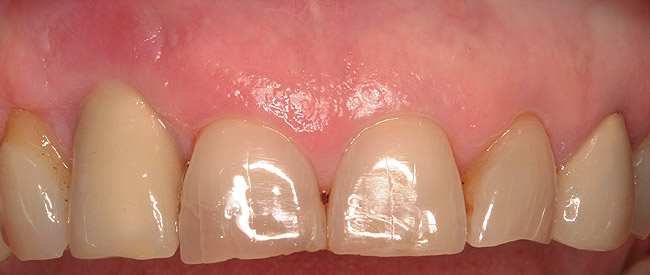

Figure 31  Final restorations in place. These are screw-retained to avoid cementation of deepened implant restorations.

Figure 31

Figure 32  Appearance of smile with crown lengthening of No. 7 (manipulated image).

Figure 32